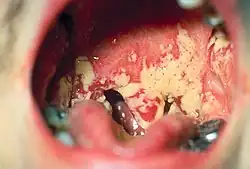

En equilibrio, la biopelícula bacteriana producida por la fermentación de azúcar en la boca es rápidamente arrastrada por la saliva, a excepción de la placa dental. En casos de desequilibrio en el equilibrio, los microorganismos orales crecen fuera de control y causan enfermedades orales como la caries dental y la enfermedad periodontal. Varios estudios también han relacionado la mala higiene bucal con la infección por bacterias patógenas.[16]

Hay muchos factores de salud bucal que deben preservarse para prevenir la patogénesis del microbioma oral o las enfermedades de la boca. La placa dental es el material que se adhiere a los dientes y consiste en células bacterianas (principalmente S. mutans y S. sanguis), polímeros salivales y productos bacterianos extracelulares. La placa es una biopelícula en las superficies de los dientes. Esta acumulación de microorganismos somete los dientes y los tejidos gingivales a altas concentraciones de metabolitos bacterianos, lo que resulta en una enfermedad dental. Si no se cuida, mediante el cepillado o el uso de hilo dental, la placa puede convertirse en sarro (su forma endurecida) y provocar gingivitis o enfermedad periodontal. En el caso de las caries dentales, las proteínas involucradas en la colonización de los dientes por Streptococcus mutans pueden producir anticuerpos que inhiben el proceso cariogénico que puede usarse para crear vacunas.[15] Se ha encontrado que las especies de bacterias típicamente asociadas con la microbiota oral están presentes en mujeres con vaginosis bacteriana.[17] Los géneros de hongos que se encuentran con frecuencia en la boca incluyen Candida, Cladosporium, Aspergillus, Fusarium, Glomus, Alternaria, Penicillium y Cryptococcus, entre otros.[5] Además, la investigación ha correlacionado la mala salud oral y la capacidad resultante de la microbiota oral de invadir el cuerpo para afectar la salud cardíaca y la función cognitiva.[8] Los altos niveles de anticuerpos circulantes contra los patógenos orales Campylobacter rectus, Veillonella parvula y Prevotella melaninogenica están asociados con la hipertensión en humanos.[18]